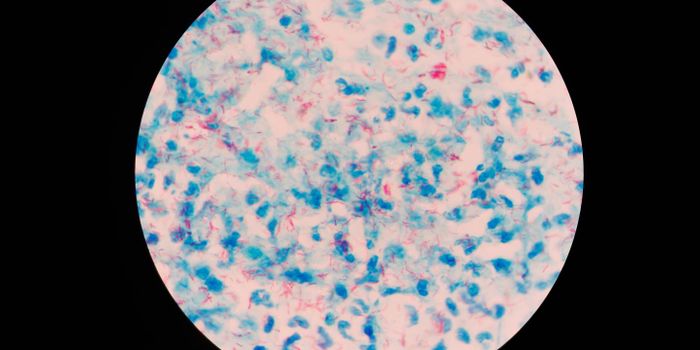

APR 19, 2022ImmunologyTuberculosis is caused by a bacterium, Mycobacterium tuberculosis, that is thought to have been around for about 150 mil ...